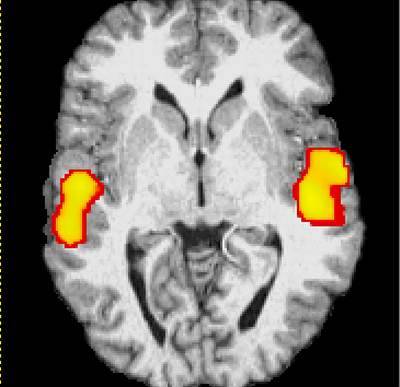

وجد علماء أمريكيون حديثاً (عام 2007) أن الدماغ يتأثر بالأصوات التي يسمعها أثناء نوم الإنسان. وبعد أبحاث طويلة تبين لهم أن دماغ الإنسان النائم يستطيع تمييز الأصوات وتحليلها وتخزينها أيضاً. وإذا علمنا أن الإنسان يمضي ثلث عمره في النوم يمكننا أن ندرك أهمية الاستماع إلى القرآن أثناء النوم كوسيلة تساعدك على حفظ القرآن دون بذل أي جهد يُذكر. ولذلك يمكن لكل واحد منا أن يستفيد من نومه ويستمع لصوت القرآن وهذا سيساعده على تثبيت حفظ الآيات. ولا ننسى قول الله تعالى عن النوم وأنه آية من آيات الله: (وَمِنْ آَيَاتِهِ مَنَامُكُمْ بِاللَّيْلِ وَالنَّهَارِ وَابْتِغَاؤُكُمْ مِنْ فَضْلِهِ إِنَّ فِي ذَلِكَ لَآَيَاتٍ لِقَوْمٍ يَسْمَعُونَ) [الروم: 23].